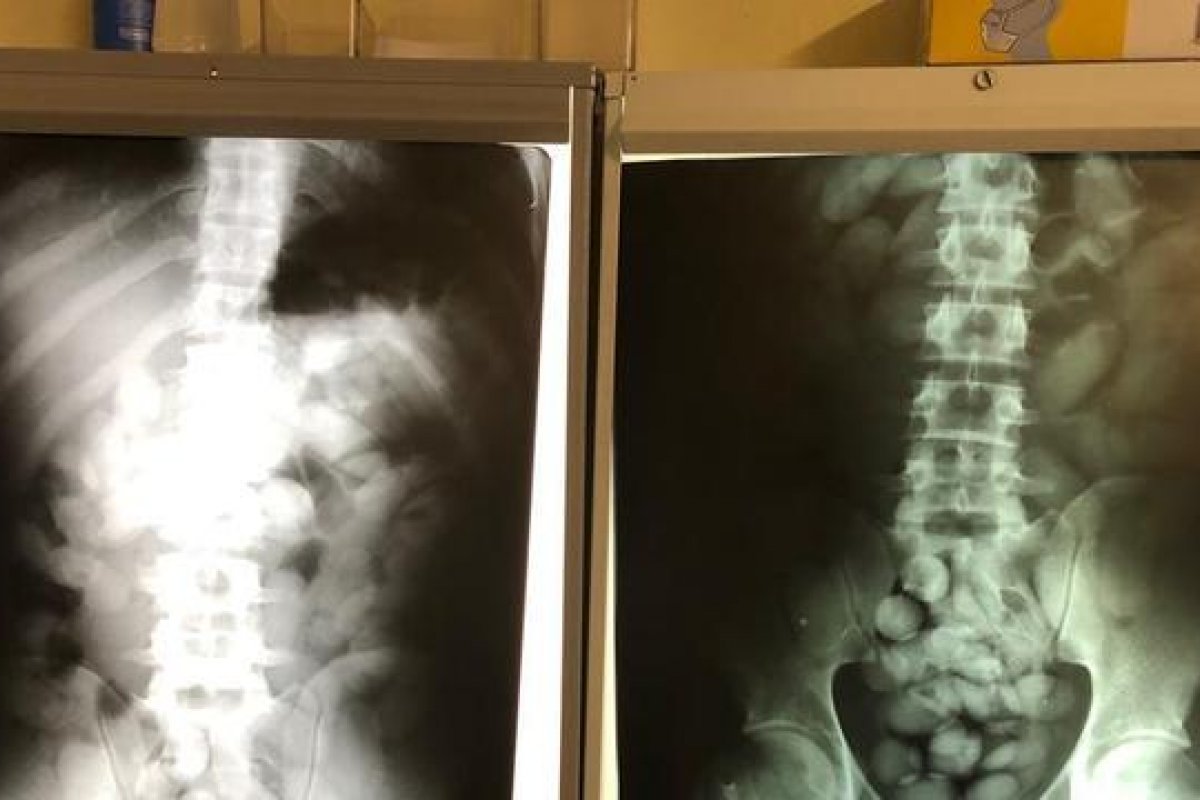

O passageiro se apresentou como brasileiro naturalizado na angola, e contou que estava indo viajar. Durante a revista, ele teria confessado que havia ingerido 100 cápsulas de cocaína e que seguiria para a Etiópia, onde esta droga seria comercializada. Com isso, ele foi detido e socorrido ao Hospital Planalto, em Itaquera, onde permanece internado sob custódia da polícia. O estado de saúde ainda não foi divulgado.